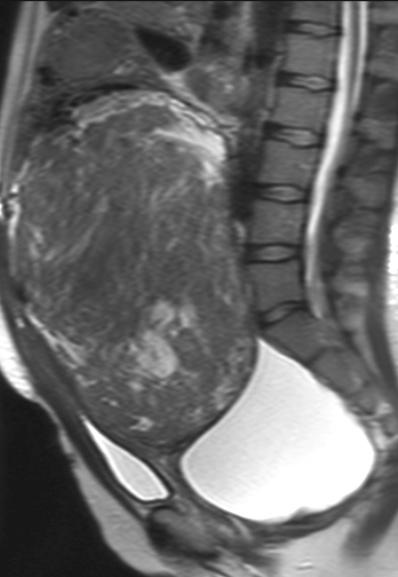

40 yold, G0 P0;MRI,较大间质内子宫肌瘤。月经稍多,肿块症状,逐渐长大。从未成功受孕;子宫肌瘤被认为是主要原因;目前不希望怀孕。因为肌瘤切除困难,妇科医生建议子宫切除。

![]() |

| 2003/03 | 2003/03 |